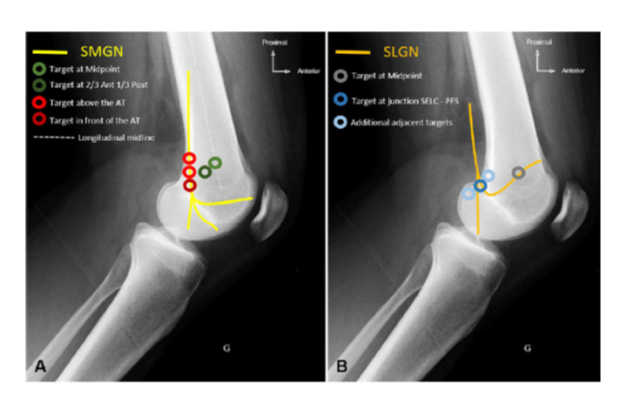

Optimization of Genicular Nerve RFA Great article with revised targets based on anatomical dissections. -Targeting the SMGN and SLGN at greater depths to improve results. rapm.bmj.com/content/45/8/6… Trent Emerick Max Eckmann

Optimization of Genicular Nerve RFA

Great article with revised targets based on anatomical dissections.

-Targeting the SMGN and SLGN at greater depths to improve results.